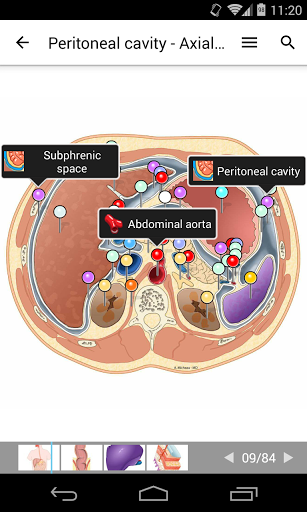

e-Anatomy memiliki lebih dari 26.000 gambar yang berisi serangkaian gambar dalam tampilan aksial, koronal, dan sagital serta radiografi, angiografi, gambar diseksi, bagan anatomi, dan ilustrasi. Semua gambar medis diberi label dengan cermat, lebih dari 967.000 label tersedia dalam 12 bahasa termasuk Terminologia Anatomica Latin.

- Gulir set gambar dengan menyeret jari Anda

- Perbesar dan perkecil

- Ketuk label untuk menampilkan struktur anatomi